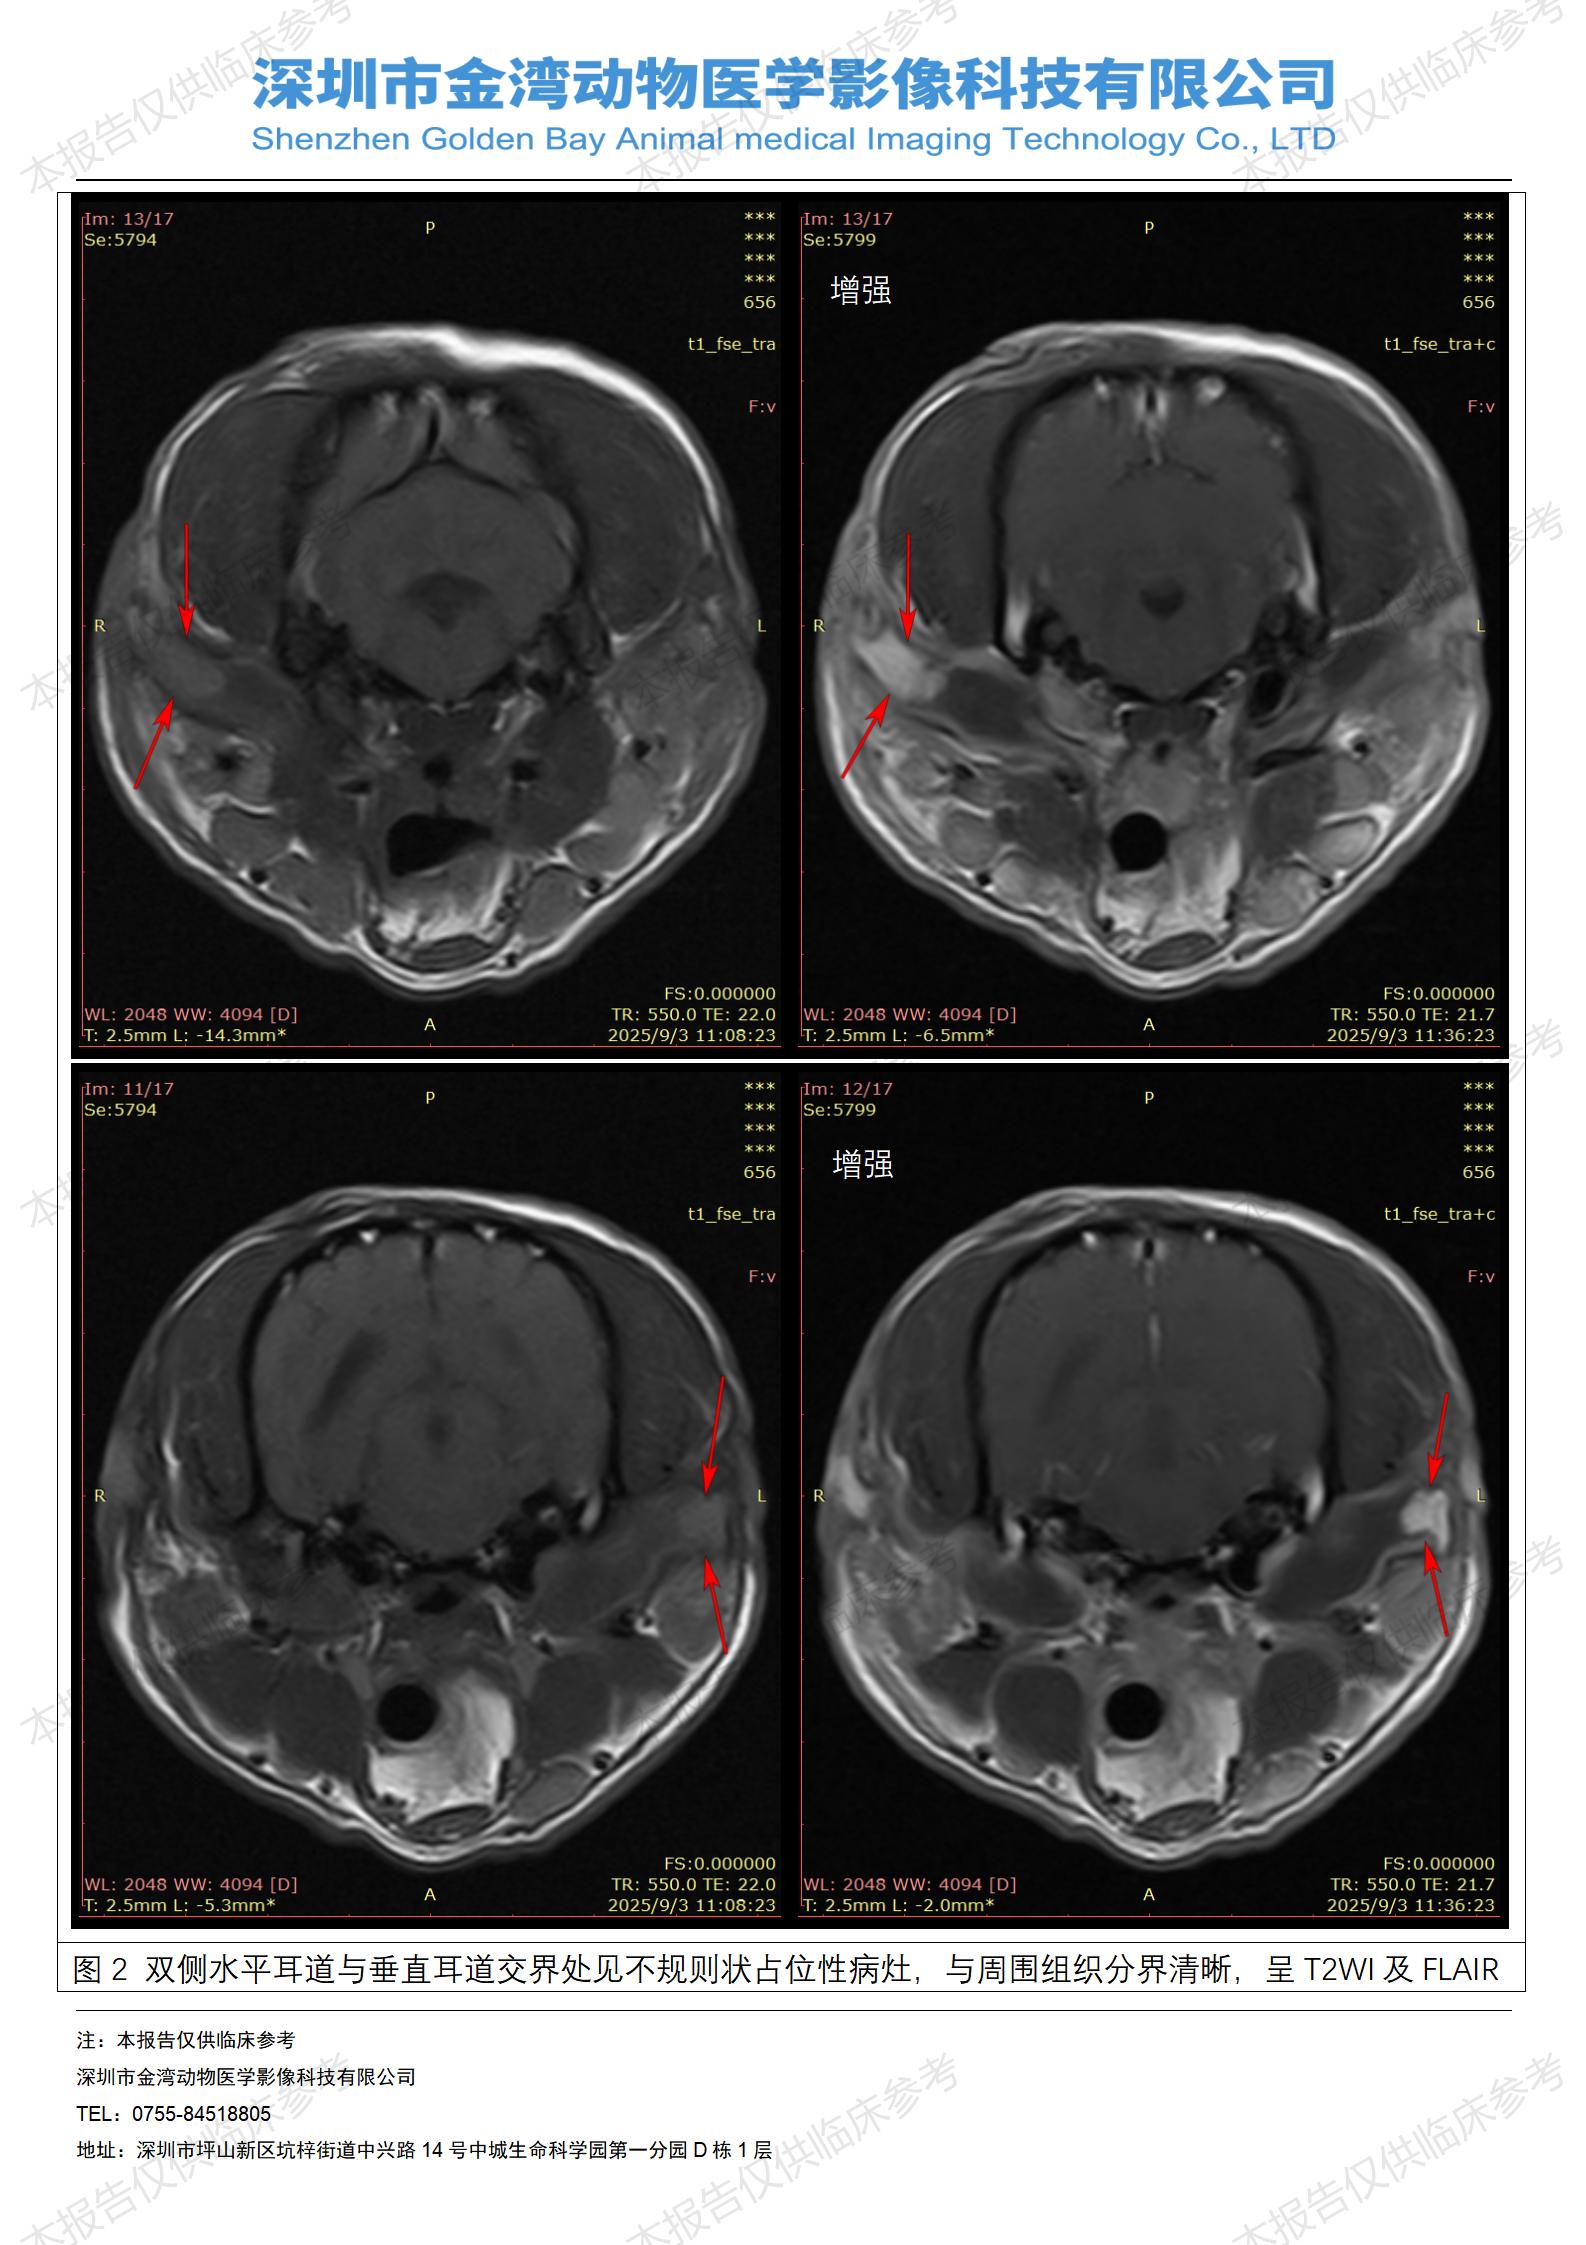

金石医疗MRI影像诊断案例:一例狗双耳流脓的诊断报告